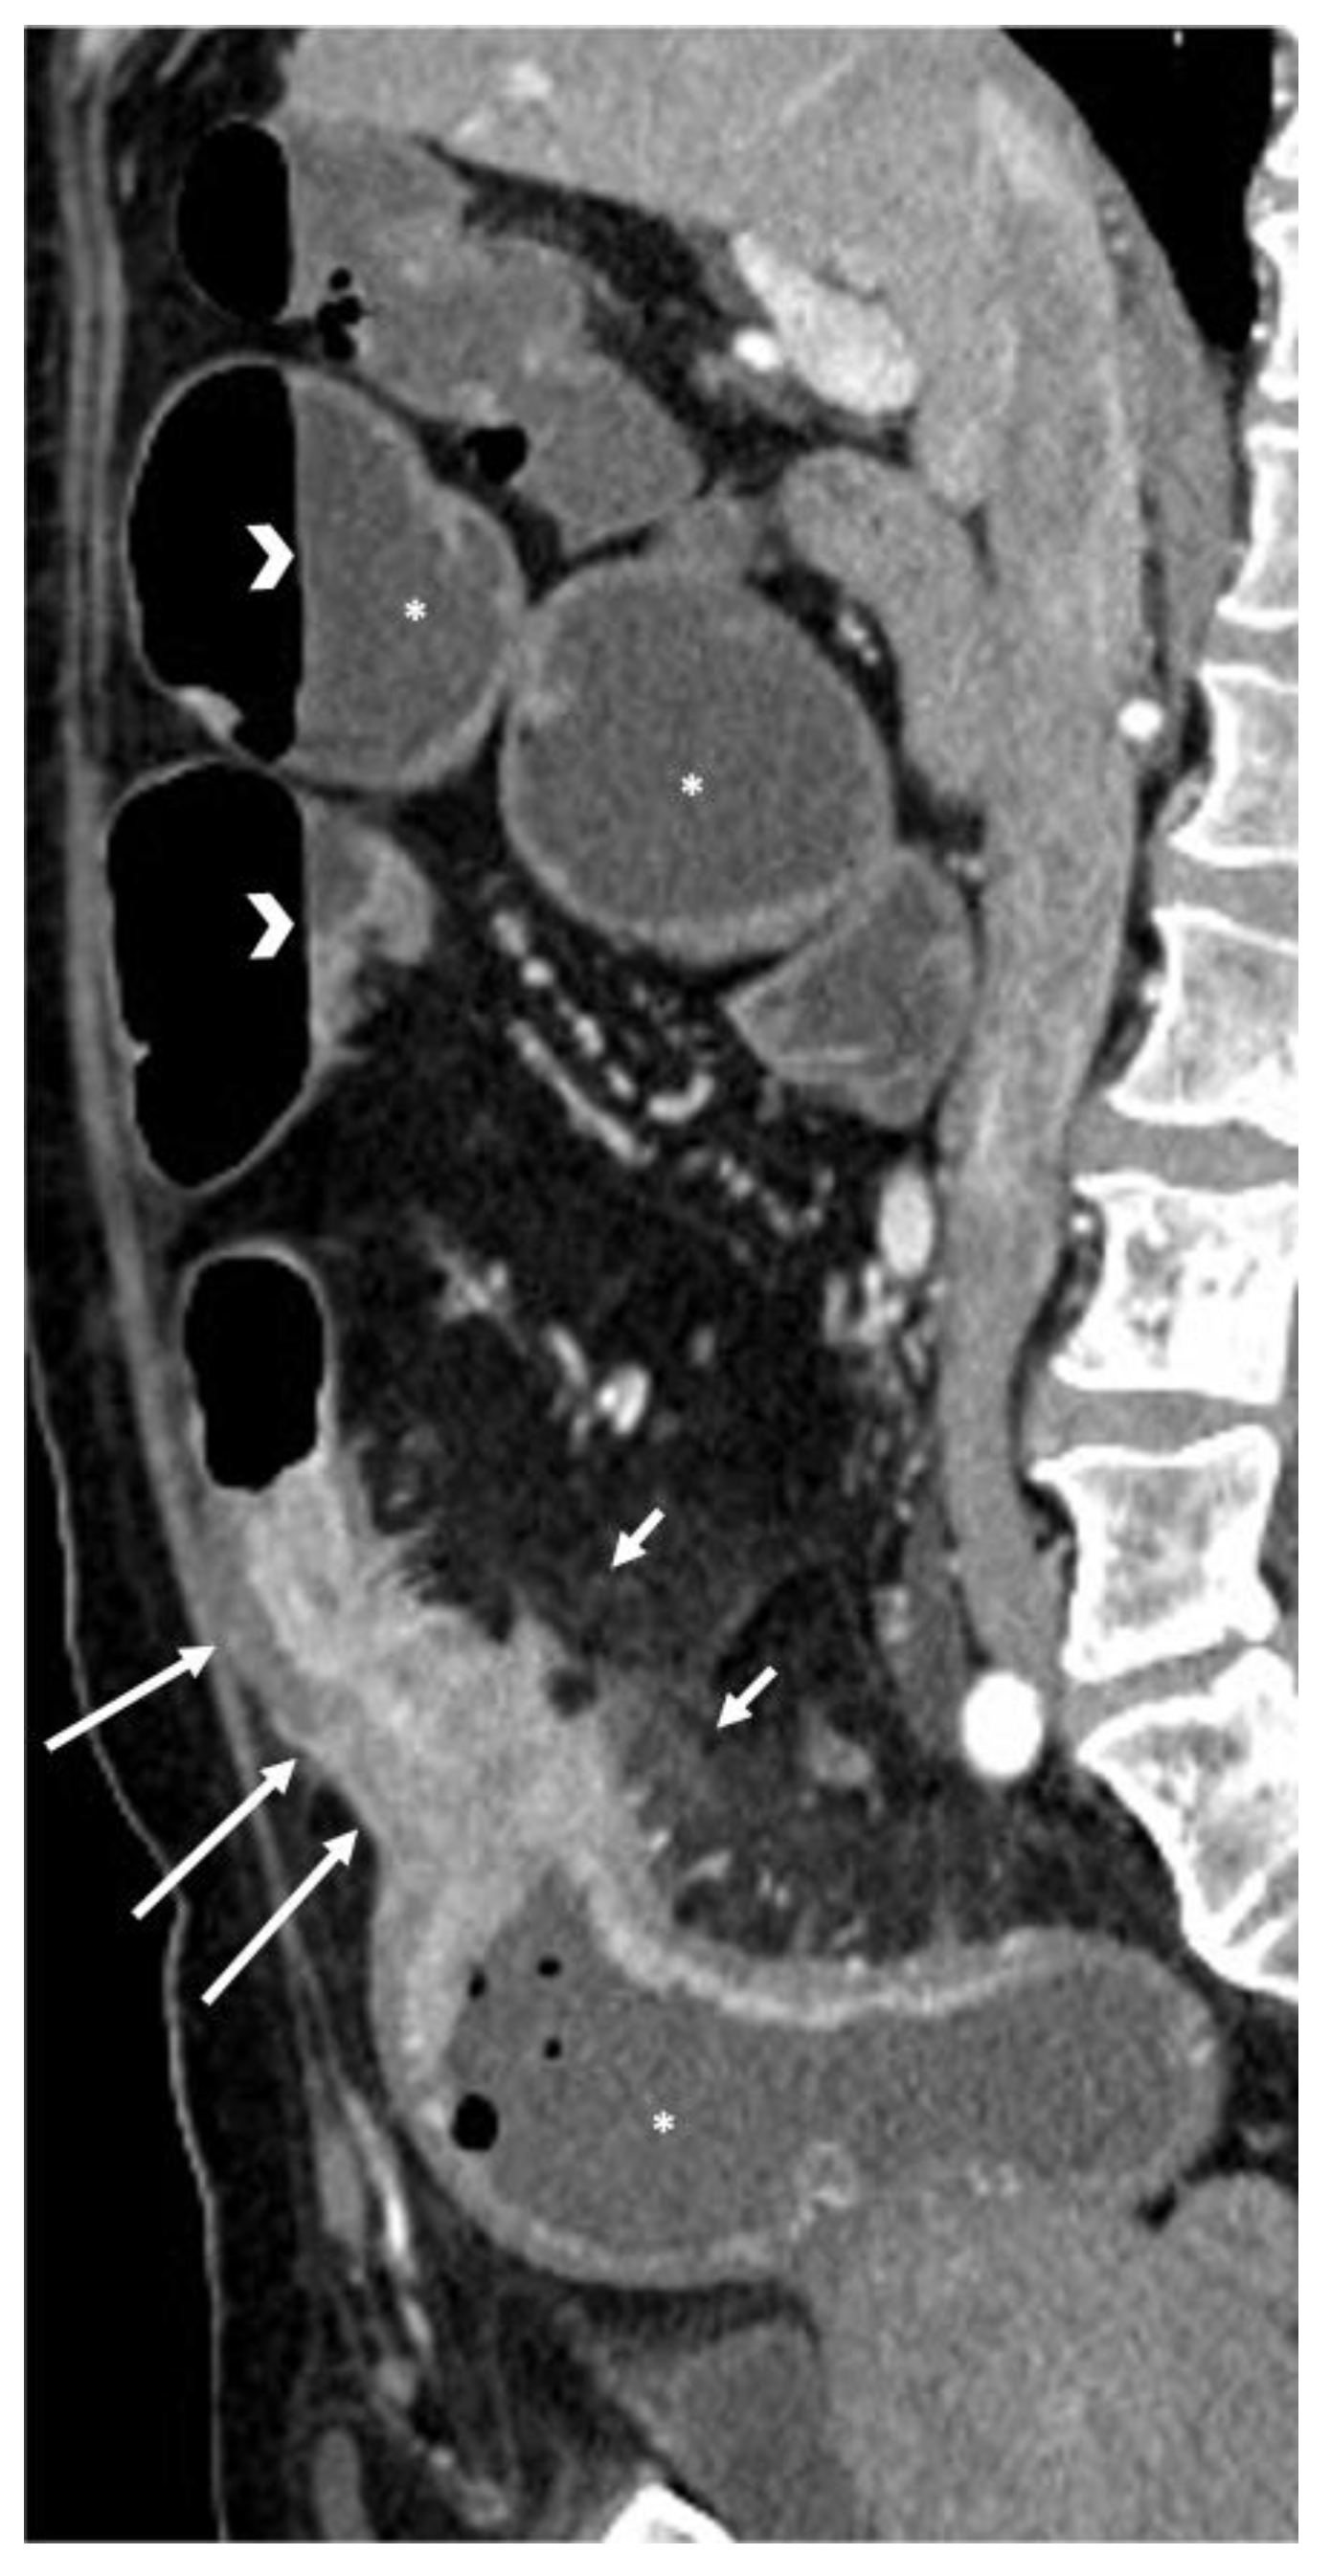

- A normal bowel loop caliber ranges between 2 and 2.5 cm. A bowel lumen is dilated when it has a maximum diameter greater than 2.5–3 cm. The dilation is mild when the upstream lumen is dilated up to 4 cm and severe when it is more than 4 cm (Figure 3) [24]. Pre-stenotic bowel dilatation should always be checked, as it is a sign related to bowel obstruction. Moderate to severe stenosis was determined via double-contrast imaging (conventional barium study) with a sufficient amount of injected air, and stenosis was defined as stenosis in which the lumen was less than one half that of neighboring healthy intestine [25].